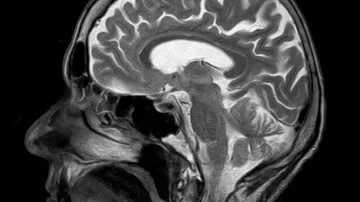

Zhruba třetina pacientů po mrtvici trpí poruchou řeči, takzvanou afázií. „Je způsobená poškozením řečových center mozku. Pokud je postiženo centrum porozumění, lidé mluví a nerozumí. Pokud centrum produkce řeči, rozumí, ale nedokážou mluvit. Vzniká takzvaný ‚slovní salát‘,“ vysvětluje primář neurologického oddělení Krajské nemocnice Tomáše Bati ve Zlíně a zakladatel Health Management Institute Robert Mikulík.

Výzkumy ukazují, že pro lidi s afázií má výrazný terapeutický přínos společný zpěv. „Na rozdíl od běžné řečové terapie aktivuje pravou mozkovou hemisféru, čímž podporuje vznik nových spojení a pomáhá nahrazovat poškozené oblasti odpovědné za jazykové funkce,“ popisuje Mikulík.